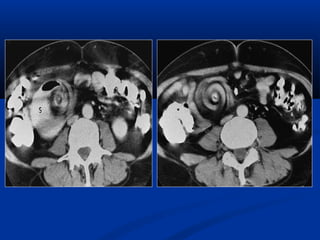

CT ÑA LÔÙP CAÉT (MULTI-SLICE )

-Nhieàu haøng detectors

-Khaûo saùt ñoàng thôøi nhieàu laét

caét

-Thôøi gian queùt nhanh (<0.5

giaây/voøng).

-Khaûo saùt toát trong caùc tröôøng

hôïp caàn thôøi gian nhanh (tim-maïch,

coù bôm caûn quang, boä phaän cöû